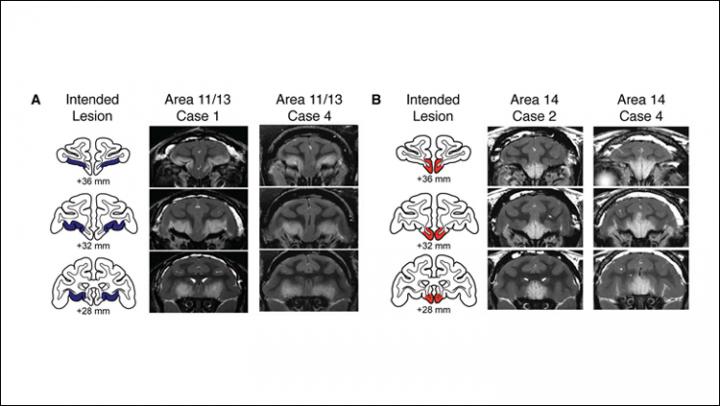

A network of brain regions including the OFC has been implicated in human anxiety disorders. For example, previous research has linked arachnophobia and generalized anxiety disorder to decreased activity in lateral and medial OFC, respectively. Elisabeth Murray and colleagues from the National Institute of Mental Health and Icahn School of Medicine at Mount Sinai investigated the role of these OFC subregions in male rhesus macaques trained to retrieve a fruit snack reward in the presence of one of two fake, rubber predators - a grayish-green snake or a black, hairy spider - or neutral objects.

After producing selective lesions in the lateral or medial OFC in eight monkeys, the researchers observed that these animals took longer to reach for the fruit snack in the presence of the predator stimuli compared to 12 animals with intact OFC. The researchers also found that this effect could be attributed to the heightened defensive and reduced approach behaviors that followed damage to either subregion of OFC. Both experimental groups also failed to reduce their defensive responses to the snake and spider over time. Finally, monkeys with medial OFC lesions showed a greater tendency to express defensive behaviors even in the absence of threat. Overall, these findings suggest that specific symptoms of various anxiety disorders may arise from dysfunction in distinct subregions of OFC.